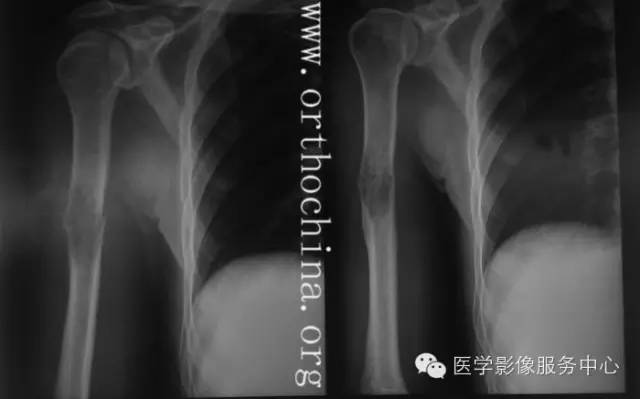

乳腺癌是最易发生骨转移的肿瘤之一,骨转移较肺癌发生的多且早。发病年龄较轻,平均45岁,据报道,在所有乳腺癌中33%~73%的病例出现骨转移。尸检中有半数以上骨转移,因此有人建议在乳腺癌手术前,常规骨骼检查,观察有无转移是很重要的。

X线片表现:基本以溶骨性破坏为主,病变开始于髓腔,自骨内向外侵蚀破坏骨皮质,病灶较广泛,常破坏骨皮质全部,一般无骨膜反应。当原发性肿瘤为硬性癌时,转移瘤多倾向成骨性,病变较局限。

混合转移瘤约占12%。